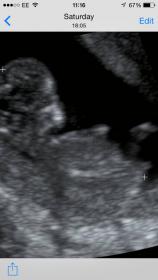

Can you see a nub?

Do you think this is a boy or girl?! :babyf:

How far along?

12 weeks :)

Exactly 12 weeks

OK, since it's early, I'm going to lean boy. It seems slightly angled upwards. But, I could be wrong of course. I guess 70/30 for boy.

Leaning boy